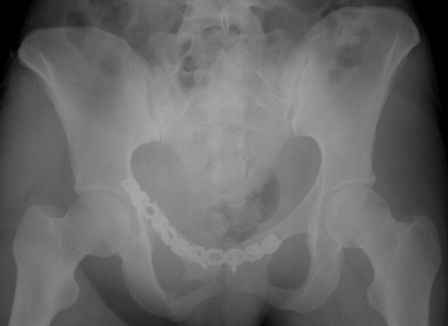

Уважаемые коллеги!

Серия до- и послеоперационных снимков этой пациентки. Хотя бы post factum обсудить. Не знаю, что можно сделать с задними отделами стержневым аппаратом, но три крепких парня открытым путем с помощью "волшебных" слов еле-еле смогли отрепонировать - сзади все было очень ригидно!

Здравствуйте, Евгений! У меня видна только дооперационная проекция inlet.